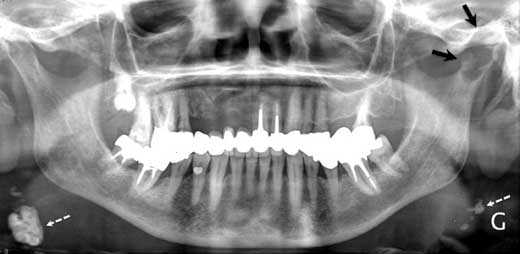

На обзорной рентгенограмме наблюдалась овальная тень с относительно чёткими контурами в головке мыщелка нижней челюсти слева (см. рис. 1). Компьютерная томография и магнитно-резонансная томография выявили объёмное образование левого мыщелка нижней челюсти, медиальную эрозию кости и отёк окружающих структур до крыловидной кости (см. рис. 2—4).

Рис. 1. На обзорной рентгенограмме видна овальная тень с относительно чёткими контурами в головке мыщелка нижней челюсти слева (показана чёрными стрелками). Белыми пунктирными стрелками показаны кальцифицированные шейные лимфатические узлы.

Рис. 2. На компьютерной томографии видны остеолитические процессы в головки мыщелка нижней челюсти слева. Зона деструкции внутренней костной пластинки отмечена белой стрелкой.

Патогномоничных рентгенологических симптомов метастаза в мыщелок немного. Как правило, на рентгенограмме такой метастаз проявляется как округлая тень.